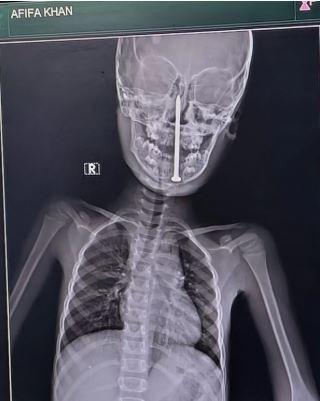

Hindistan'da gerçekleşen olağanüstü bir ameliyatla, doktorlar 7 yaşındaki bir kızın beynine saplanan 8 santimetrelik çiviyi başarıyla çıkardı.

Küçük kız oyun oynarken düştü ve yerdeki ince bir inşaat çivisi, boynunu ve çenesini delerek beynine kadar ulaştı. Korkunç olay, 15 Mayıs'ta Uttar Pradesh eyaletinin Nawajpur köyünde meydana geldi.

Yapılan tomografi, çivinin alt çeneden girip kafatasına kadar ilerlediğini ve hayati damarların çok yakınından geçtiğini gösterdi. Ameliyat, ertesi gün (16 Mayıs'ta) Dr. Vaibhav Jaiswal ve Dr. Sameer Mishra tarafından Lucknow'daki King George Tıp Üniversitesi Travma Merkezi'nde yapıldı.